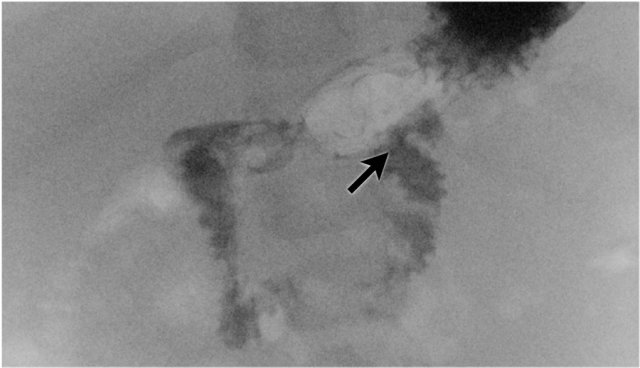

First look at the images of the upper GI-study and describe the findings.

Then continue reading.

The findings are:

- Dilated proximal duodenum (asterix)

- Small amount of contrast passes through the duodenal web to the distal duodenum (arrow)